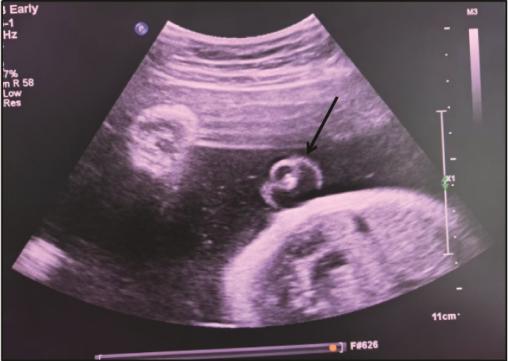

Objective: To analyze the clinical profiles of parturients with umbilical vascular thrombosis, to delineate early recognition markers and diagnostic-therapeutic protocols, and to provide evidence for optimizing maternal-fetal outcome. Methods: Clinical data of 6 parturients with umbilical vascular thrombosis managed at Shenzhen Guangming District People's Hospital were retrospectively reviewed. Results: Among the 6 cases, 5 cases exhibited abnormal antepartum cardiotocography (CTG). Prenatal ultrasound identified umbilical vascular thrombosis in 3 cases, all delivered by emergency cesarean section promoted by pathological CTG patterns. Within this subgroup, one fetus presented with a secondary single umbilical artery and one with markedly tight umbilical cord spirals; the latter received a complete course of antenatal corticosteroids for fetal pulmonary maturation after sonographic detection of umbilical arterial thrombosis at 31+1 weeks, followed by emergency cesarean section at 34+4 weeks. In the remaining 3 cases, prenatal ultrasound revealed no umbilical vascular anomaly; 2 cases underwent emergency cesarean section for abnormal CTG and one had an elective cesarean section. All 6 neonates survived. Of the 5 parturient-neonate pairs screened for protein S and protein C activity, 4 mothers were deficient in protein S and 2 in protein C; 3 neonates were deficient in protein S and 5 in protein C. Conclusions: Whenever obstetric ultrasound indicates an altered umbilical vessel count, hyper-coiled umbilical cord, laboratory evidence of protein S or protein C deficiency, or abnormal CTG patterns, umbilical vascular thrombosis should be suspected. In preterm pregnancies with stable fetal status, expectant management under intensive surveillance may be considered.